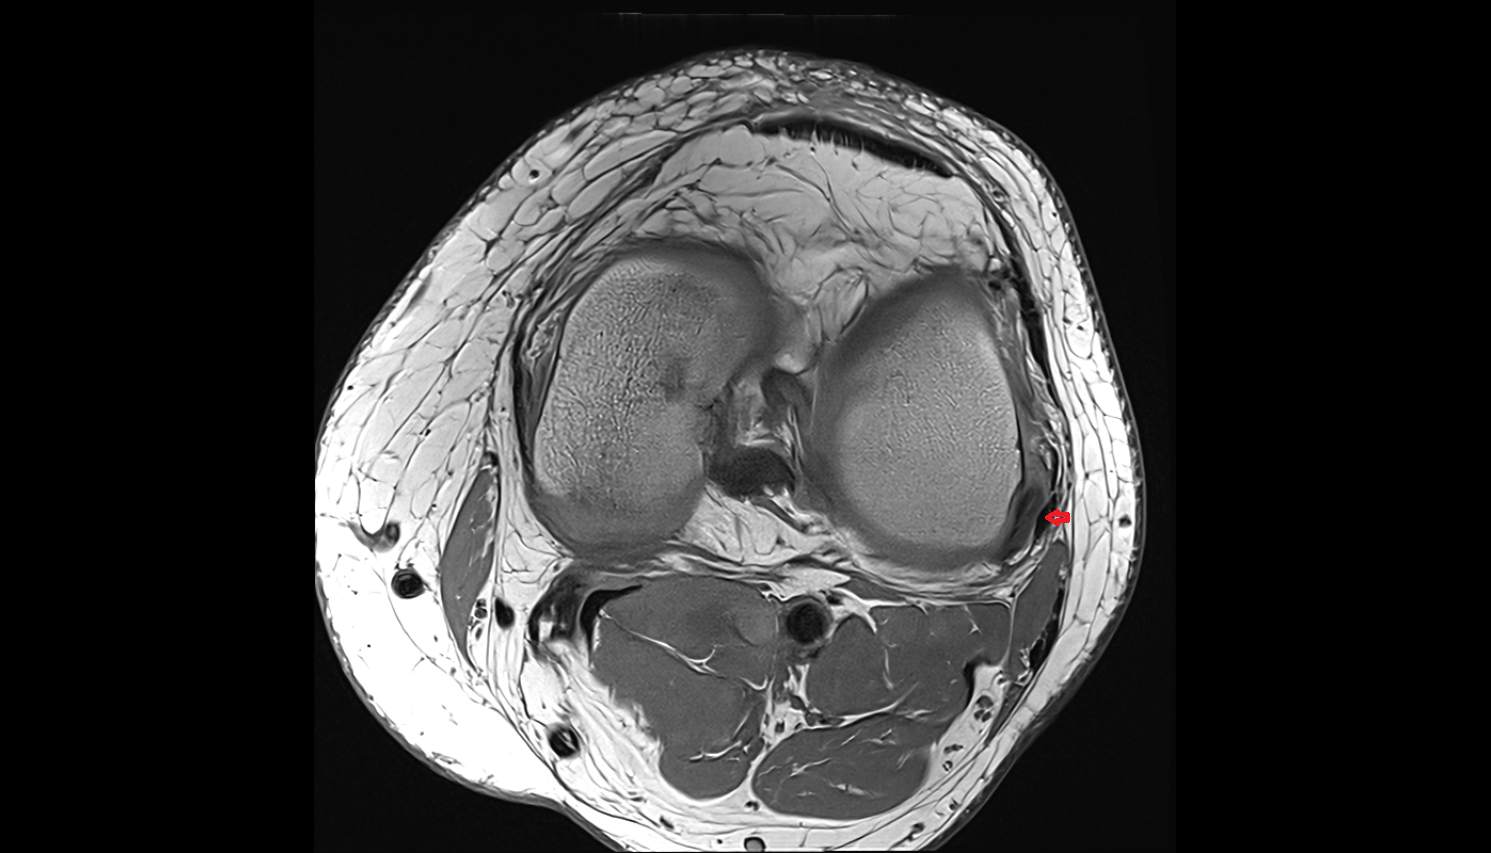

- Knee Joint